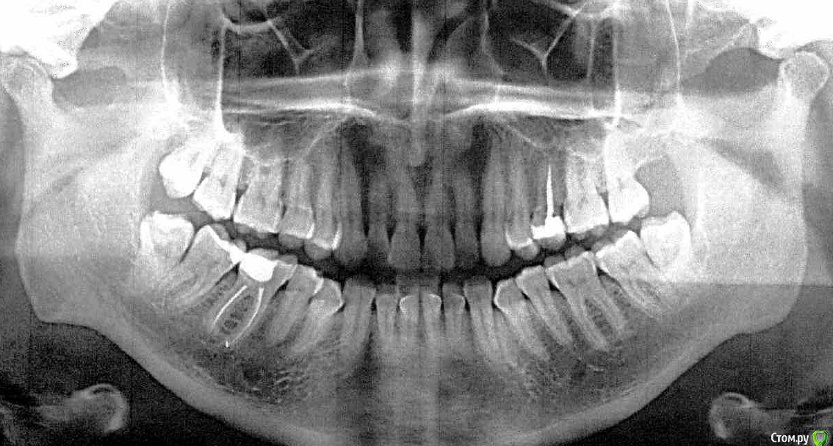

Nika07 Опубликовано 20 апреля, 2017 Поделиться Опубликовано 20 апреля, 2017 (изменено) Всем доброго дня! Рассказываю свою эпопею и заранее благодарю за советы.У меня такая ситуация: треснул 25 зуб.Зуб ранее леченый, без нерва, лет 7 назад удаляли нерв и ставили анкерный штифт.Во время еды - хрясь - и треснул вертикально. Побежала к врачу, выходной был - сделали рентген, врач отломал кусок зуба.Затем вроде собирались коронку делать, я согласилась. Потом в глубину сверлил врач и сказал, что трещина глубоко в корень уходит и коронку ставить не получится. Пришел другой врач - консилиум устроили - и посоветовал запломбировать зуб как клык - т.е. на одной стенке, и все.Потом, в будни, пошла к своему стоматологу, она говорит, лучше коронку делать. Насчет трещины сказала - что тогда болел бы, если б трещина в корне была. Зуб не болел абсолютно ни когда треснул, ни во время всех манипуляций с ним. Пошла к ортопеду - говорит, можно коронку, но тогда надо сначала его вытянуть брекетами, т.к. отлом под десной. Это около полугода брекет на нем носить, потом коронку делать. Вот, собственно вопрос - что лучше делать - брекет и коронку потом? Или пусть стоит сколько стоит, в виде клыка, а если вдруг сломается или еще что - (на одной стенке все-таки) - имплант тогда придется делать? С одной стороны, жаль зуб, с другой, вытягивания боюсь, не навредит ли это? Заранее спасибо за советы! Изменено 20 апреля, 2017 пользователем Nika07 Ссылка на комментарий

AndyAndy Опубликовано 20 апреля, 2017 Поделиться Опубликовано 20 апреля, 2017 На вашем месте я бы решал или вытягивание брекетом + коронка, или имплантация. Минусы первого варианта: время, укорочение длины корня зуба, стоимость перелечивание+культевая вкладка+коронка. Немедленная имплантация при удалении зуба: по стоимости не думаю что будет чересчур сильно отличаться от первого, по времени так же, по надежности - лучшая стабильность конструкции.Для оценки проведения имплантации необходимо КТ Однозначного ответа на ваш вопрос нет. Если есть невероятное желание сохранить зуб без гарантий, то занимайтесь им. Я за имплантацию 1 Ссылка на комментарий